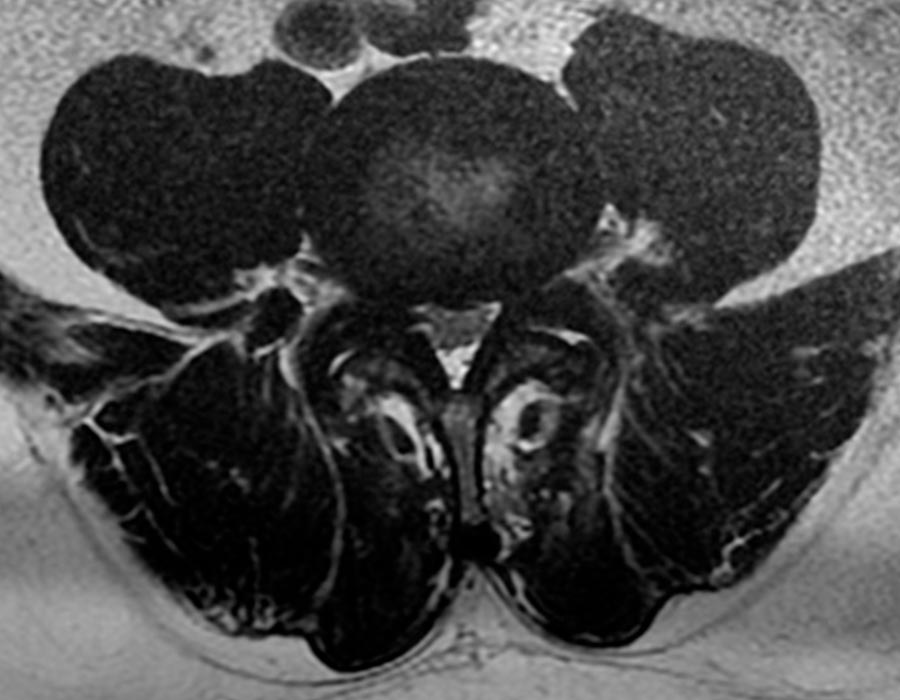

Tras la observación del caso, diagnosticamos una estenosis de canal central L4L5 con signos de compresión radicular en el territorio de L4L5 y L5S1 lo que provocaba una claudicación neurógena y le estaba impidiendo andar con normalidad.

Con la realización de una resonancia magnética observamos además una severa degeneración del disco mencionado y una hipertrofia facetaria acompañando a la estenosis de canal detectada anteriormente.